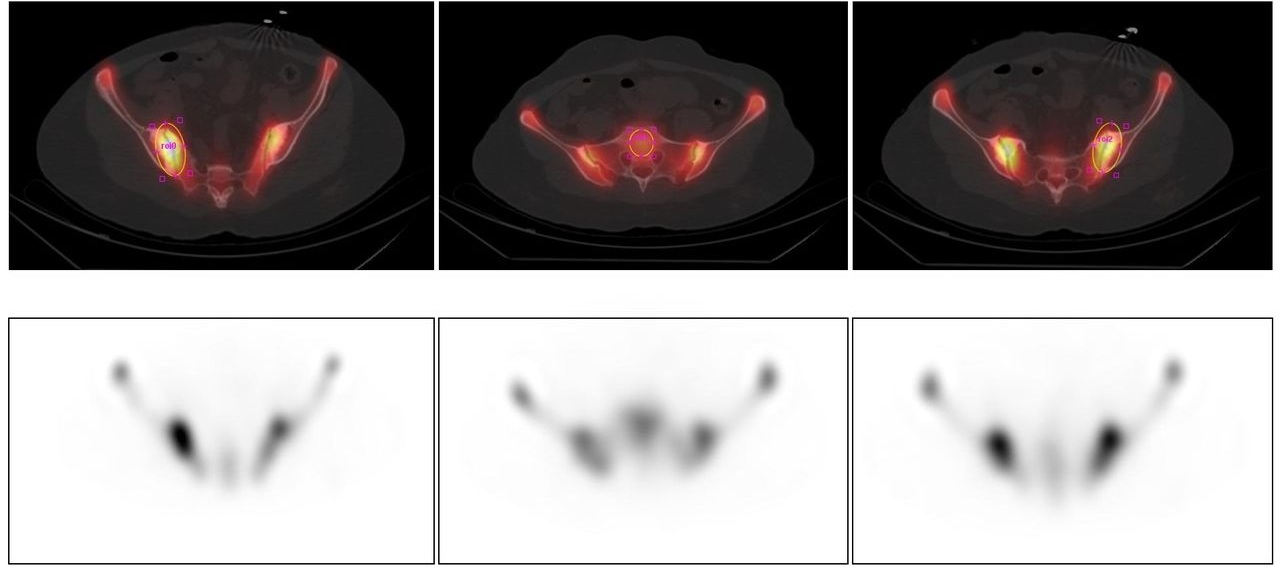

Le immagini illustrano 6 approcci per valutare il SII.

Scintigrafia planare (metodi 1-4): calcolo del rapporto di captazione tramite ROI rettangolari globali (1), irregolari anatomiche (2), a profilo grafico orizzontale (3) o rettangolari suddivise in metà superiore/inferiore (4). SPECT (metodo 5): valutazione qualitativa (visual scoring) che confronta visivamente l’intensità delle articolazioni sacro-iliache rispetto al sacro (minore, uguale o maggiore). SPECT/TC (metodo 6 – immagini assiali): analisi quantitativa 3D tramite VOI. L’integrazione delle metodiche tomografiche (metodi 5 e 6) aggiunge valore e precisione quantitativa rispetto alle sole tecniche planari.